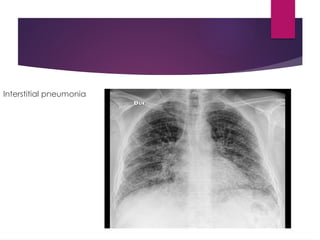

Anatomical classification

Lobar pneumonia Bronchopneomonia

Interstitial pneumonia